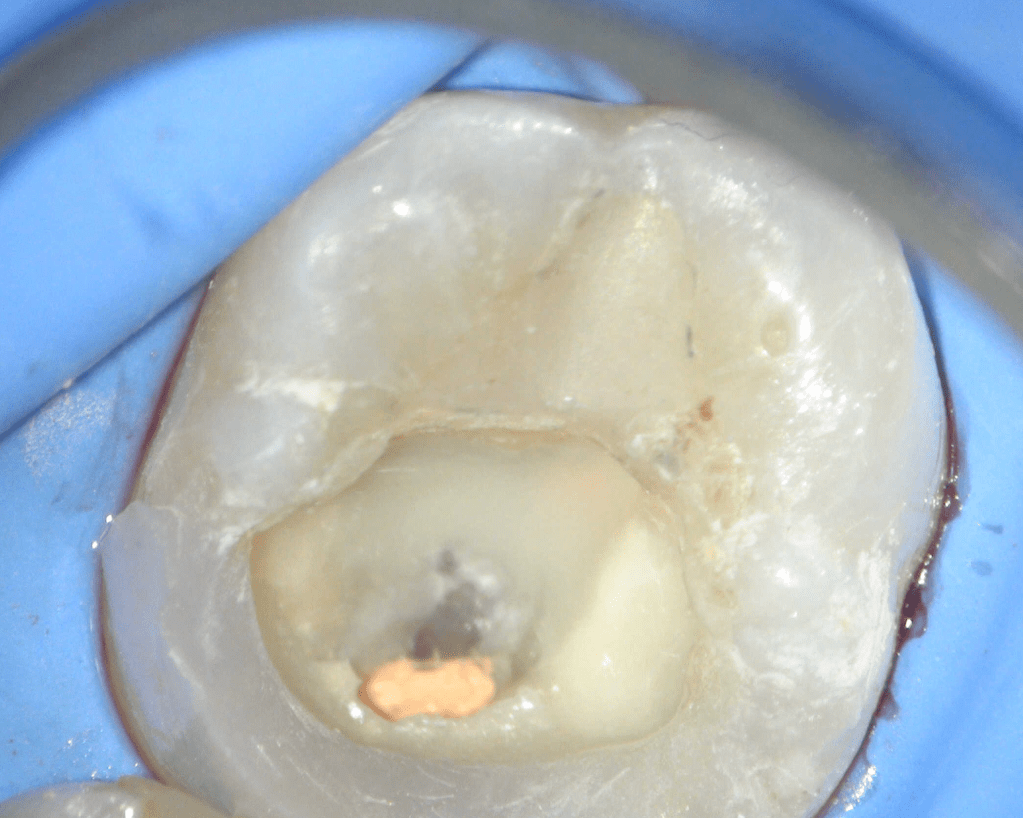

Reco preendo + 4 conductos molar superior